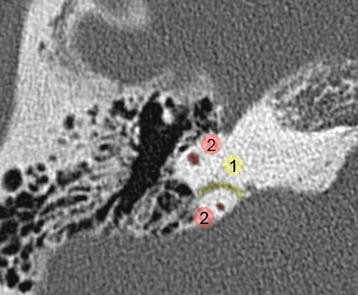

This gallery of images presents the anatomy of the temporal bone by means of ct scan reconstructions. The temporal bones comprise the lateral skull base forming portions of the middle and posterior fossae. This atlas allows you to scroll through ct slices of the temporal bone in four different planes.

In this review we present the normal axial and coronal anatomy of the temporal bone by scrolling through the images. Computed tomography ct has revolutionized imaging of the temporal bone. Given that the file is large loading may take a few minutes.